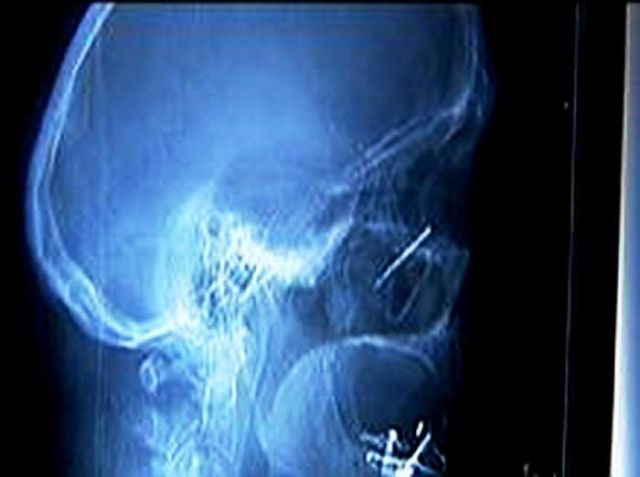

These x-rays will make you wonder how this could ever have happened in the first place.